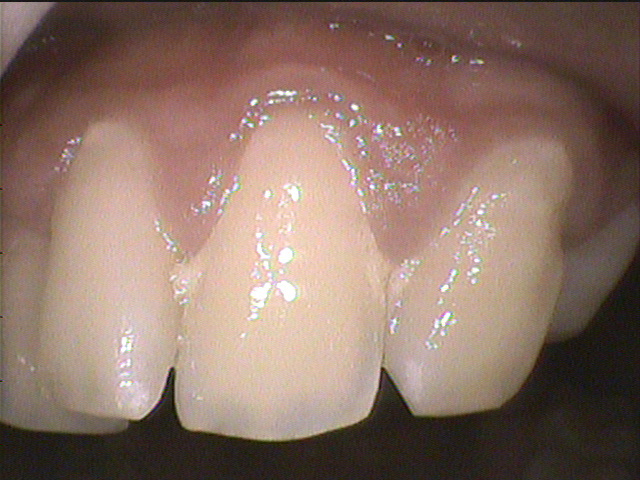

◎クリーニング前

フロスをほとんど使えていなかったそうで、歯間部にプラーク(歯垢)と歯茎に炎症がありました。

歯と歯が重なっているところは歯ブラシが当たりづらいため、歯石やプラーク(歯垢)がつきやすい場所です。